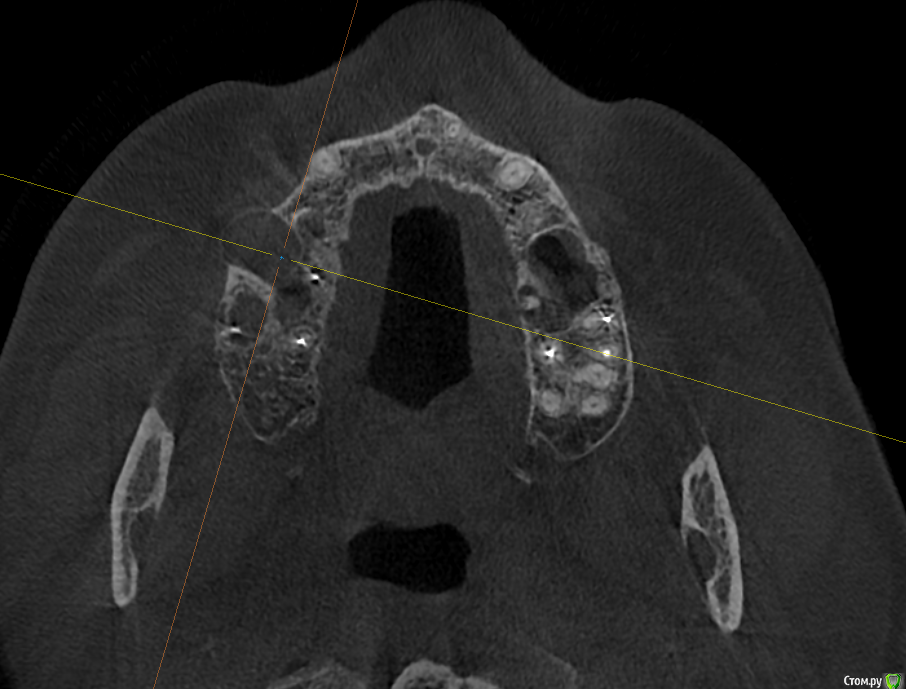

Raystom Опубликовано 20 февраля, 2021 Поделиться Опубликовано 20 февраля, 2021 Обратилась пациентка с неприятными ощущениями в области зубов 26, 27, во рту эти зубы показались мне темнее остальных, на КТ видна вот такая красота. Каков план лечения в таких ситуациях? Попробовать отделить пазуху от грануляций или просто удалить и после лечения ЛОРа идти на закрытие ОАС? Как после восстанавливать кость? И какие временные промежутки. Понимаю, что многие скажут при таких вопросах передать другим, но это не мой вариант. Мб есть литература по подобным случаям? Ссылка на комментарий

Карен Аванесов Опубликовано 22 февраля, 2021 Поделиться Опубликовано 22 февраля, 2021 Обратилась пациентка с неприятными ощущениями в области зубов 26, 27, во рту эти зубы показались мне темнее остальных, на КТ видна вот такая красота. Каков план лечения в таких ситуациях? Попробовать отделить пазуху от грануляций или просто удалить и после лечения ЛОРа идти на закрытие ОАС? Как после восстанавливать кость? И какие временные промежутки. Понимаю, что многие скажут при таких вопросах передать другим, но это не мой вариант. Мб есть литература по подобным случаям?Аккуратно удалить, убрать грануляции, инструментально уточнить есть ли сообщение с пазухой (Думаю что нет), если и есть, коллаген, и лунку ушит. Динамичный контроль. Ссылка на комментарий

колесников Опубликовано 25 февраля, 2021 Поделиться Опубликовано 25 февраля, 2021 Киста сделала синуслифтинг,этот объём надо сохранить,колапол резорбируется быстро и через 3-6 мес останется 3мм,графт не скиснет,а созреет по форме дефекта,надо избежать вторичного инфицирования. Перекрыть вестибулярным лоскутом лунку не получится,раскрытие-инфицирование,боль,отёк,контрактура,смешение биотипа. Зачем? Можно нёбный мобилизовать или выбрать другой способ герметичного закрытия лунки Ссылка на комментарий

Raystom Опубликовано 25 февраля, 2021 Автор Поделиться Опубликовано 25 февраля, 2021 Киста сделала синуслифтинг,этот объём надо сохранить,колапол резорбируется быстро и через 3-6 мес останется 3мм,графт не скиснет,а созреет по форме дефекта,надо избежать вторичного инфицирования. Перекрыть вестибулярным лоскутом лунку не получится,раскрытие-инфицирование,боль,отёк,контрактура,смешение биотипа. Зачем? Можно нёбный мобилизовать или выбрать другой способ герметичного закрытия лункиПонятно, спасибо, буду делать Ссылка на комментарий